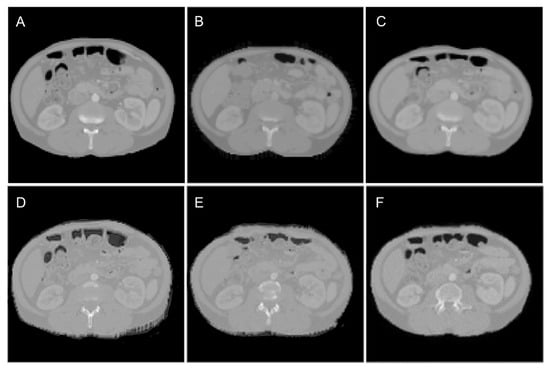

2.1. Data Preparation

2.3. Training and Testing of the Model